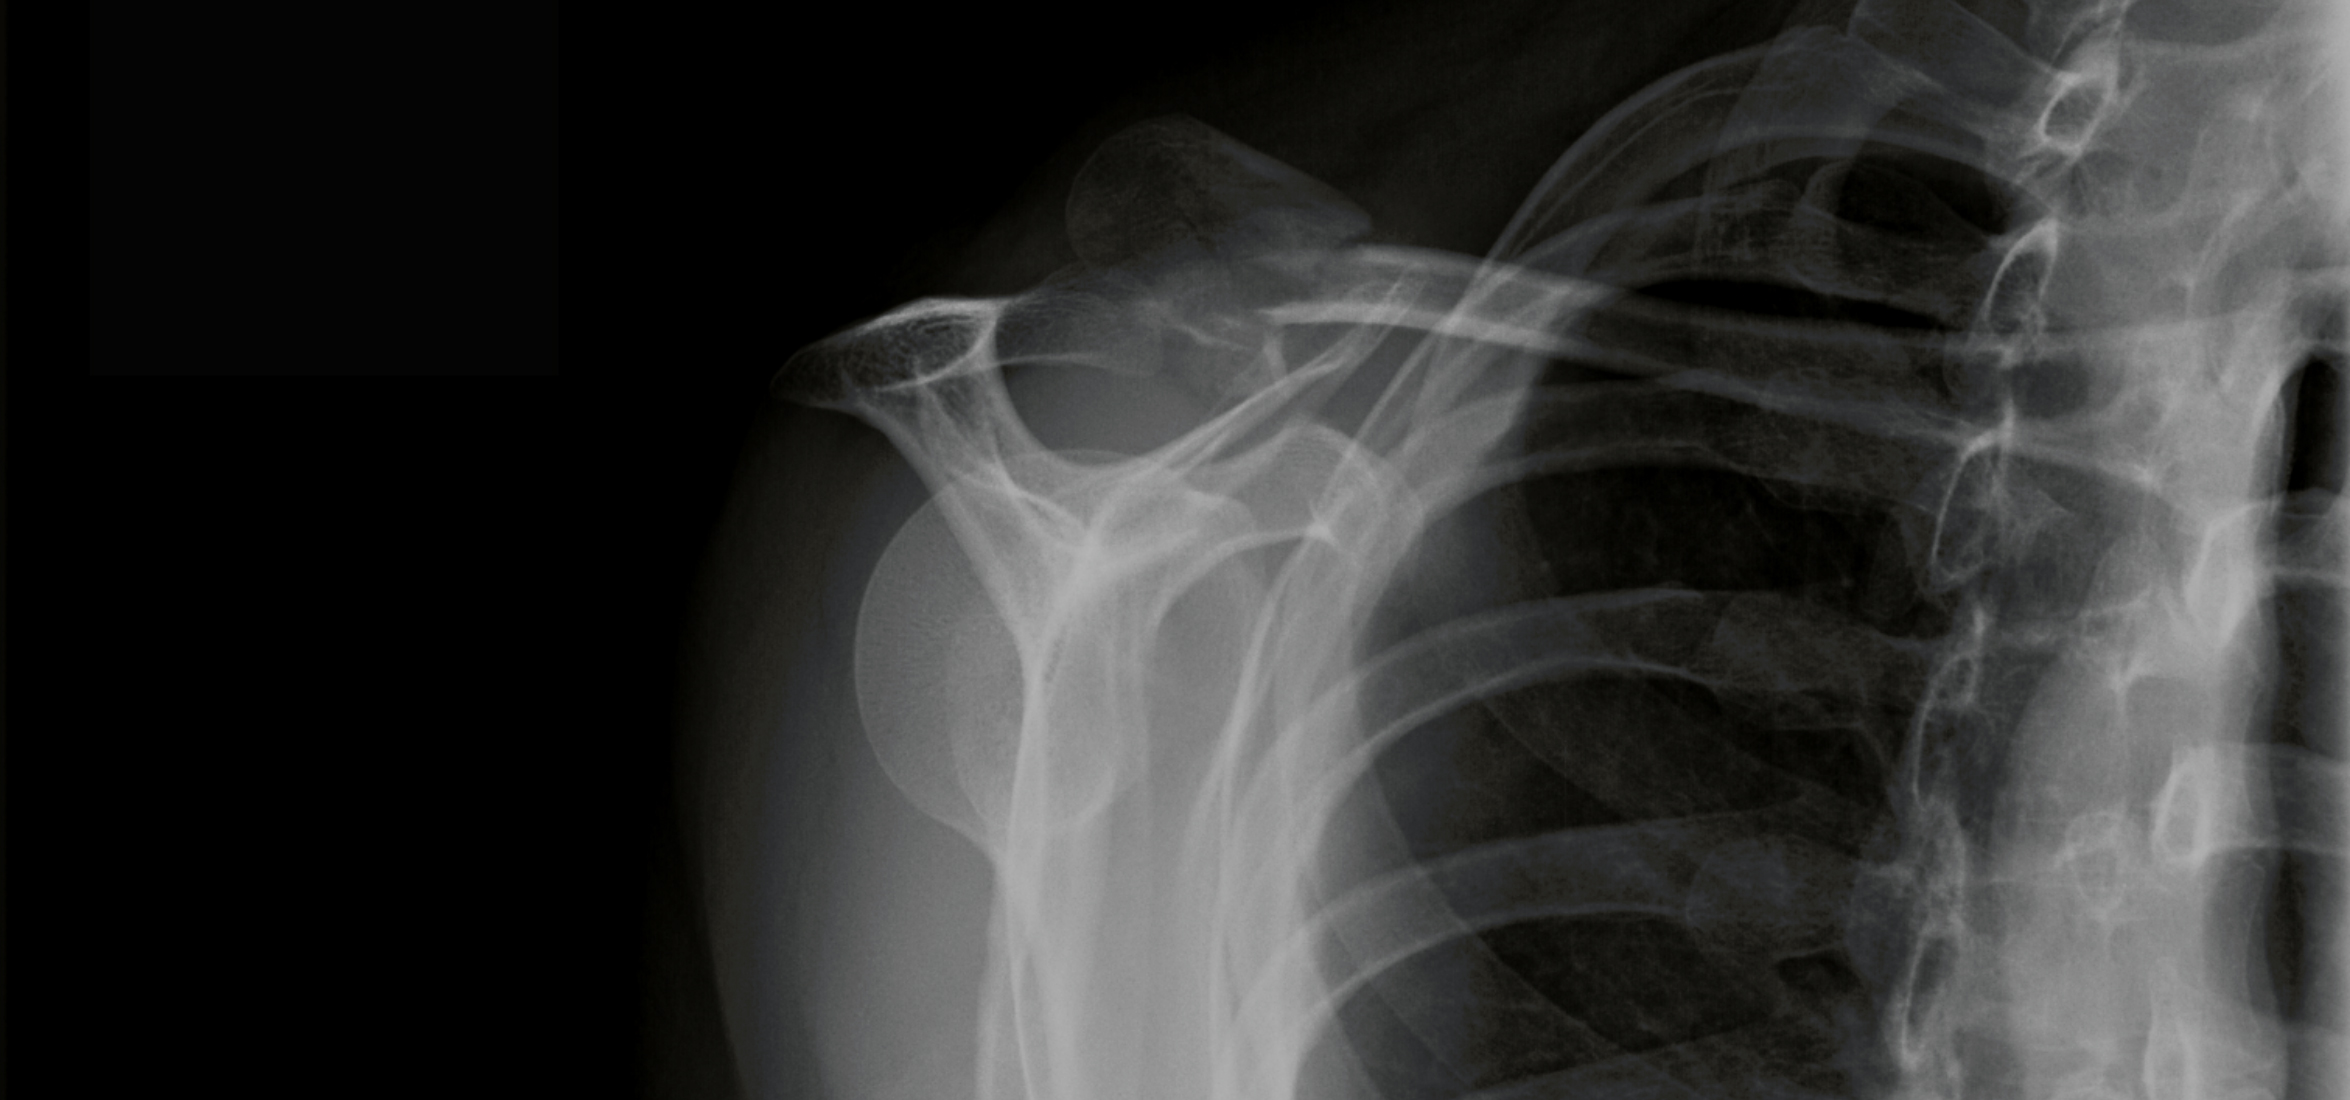

Bone Xray.

People living with type II diabetes and hypertension face an increased risk of bone fractures. An international team of researchers has used the Canadian Light Source (CLS) at the University of Saskatchewan (USask) to identify a potential bone health therapy that could one day alleviate that problem.

The collaboration between the Bone-Muscle Research Center at the University of Texas at Arlington (BMRC-UTA) and the Colleges of Medicine and Kinesiology at USask explored whether hepatocyte growth factor (HGF) could help reduce the fracture risk for people with type II diabetes. Since 50-85 % of diabetic patients live with hypertension, and both conditions are linked to a higher risk of breaks, this population is particularly vulnerable.